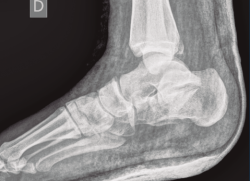

Figura 12. Radiografía de perfil a los 9 meses de la cirugía.

A los 9 meses únicamente presentó dolor ocasional al nivel de la articulación subastragalina y molestias en la planta del pie al deambular descalzo, por lo que se pauta plantilla amortiguadora, con la que mejora notablemente la sintomatología. Presentó una puntuación de 83 sobre 100 en la escala de la American Orthopaedic Foot and Ankle Society (AOFAS), ligeramente superior a la media descrita en estudios previos(2,3). Radiográficamente se evidenció una anatomía restablecida del calcáneo y de la sindesmosis, así como una altura adecuada de ambos tobillos (Figuras 12 y 13). Dada la buena evolución, se decidió continuar con el seguimiento anual del paciente sin realizar la extracción del material de osteosíntesis, para valorar la necesidad de una futura artrodesis sub­astragalina.